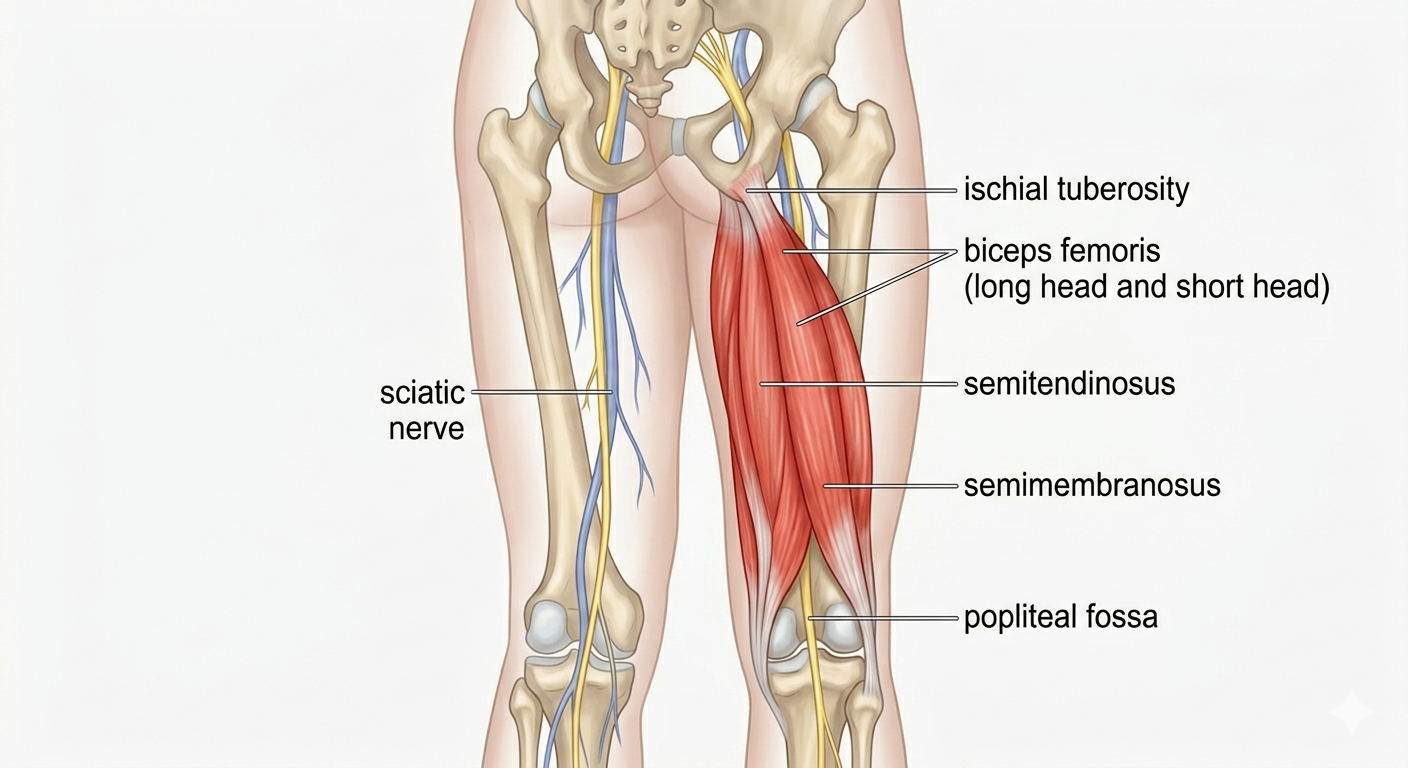

Anatomy of the Hamstrings: A Quick Overview

The hamstrings are a group of three muscles. They run along the back of your thigh. These are the semitendinosus, semimembranosus, and biceps femoris. They originate from the ischial tuberosity (sit bone).

These muscles insert just below the knee joint. Their primary functions include knee flexion and hip extension. Understanding this anatomy helps target muscles effectively. It ensures a comprehensive hamstring exercise program. More about Hamstring